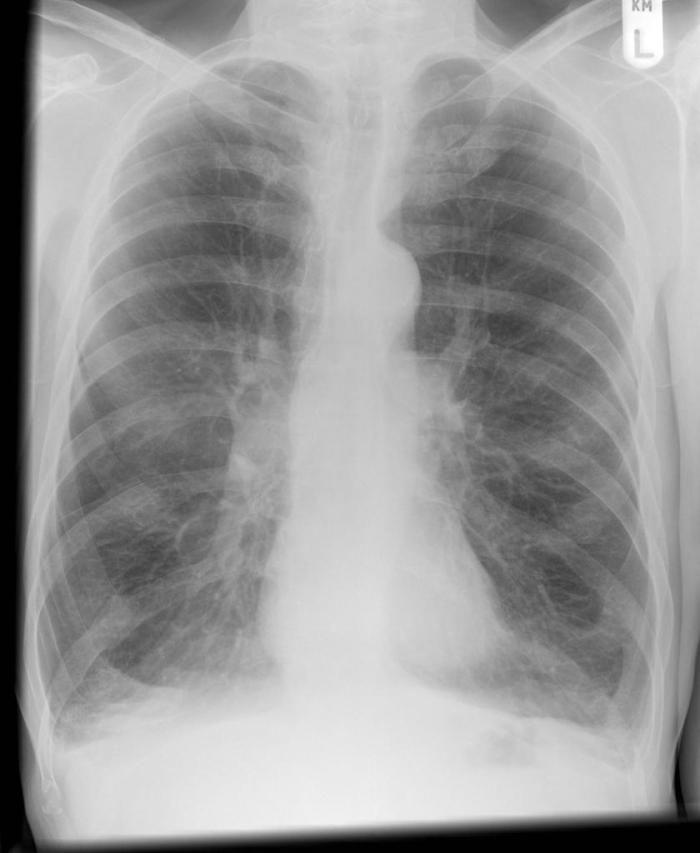

CXR for the case found here:

Image courtesy of Dr Jeremy Jones, Radiopaedia.org, rID: 6410